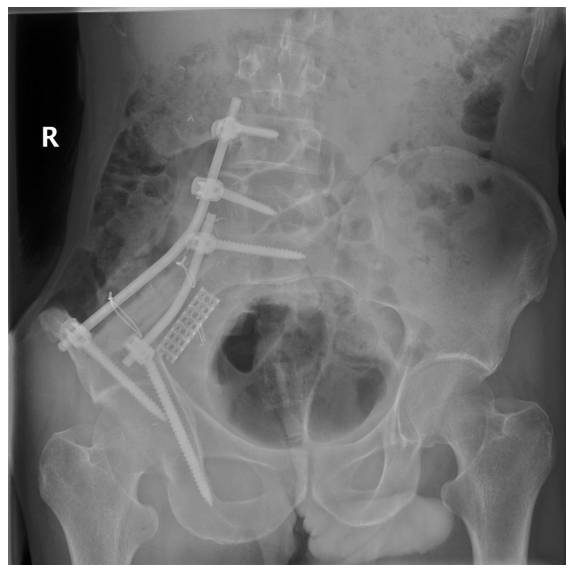

Hastaya internal hemipelvektomi ve rekonstrüksiyon (vaskülerize fibula ve titanyum kafes ile lumbopelvik fiksasyon) uygulandı

Ameliyat Sonrası: Röntgende rezeksiyon sonrası fibula ve titanyum cage ile yapılan lumbopelvik fiksasyon görülmekte